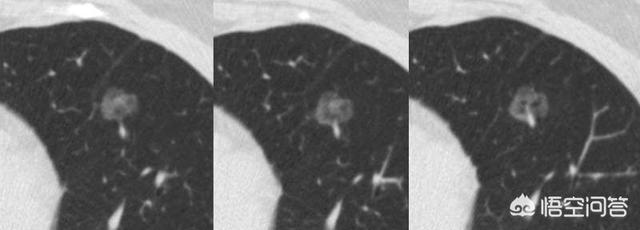

Der Pfeil zeigt auf den Knoten, der sehr klein war, als er im März 2016 entdeckt wurde, etwa 0,5 cm, und jetzt werden bei Routineuntersuchungen sehr viele Knoten wie dieser entdeckt.Es gibt keine Möglichkeit, auf den Bildern festzustellen, ob es gut- oder bösartig ist, sondern nur die Möglichkeit der Überprüfung, und die Überprüfung und Nachsorge ist auch das beste Mittel.

Sieben Monate später, bei der zweiten Nachuntersuchung im Oktober 2016, wurde deutlich, dass dieser Knoten größer und runder geworden war. Der vergrößerte Knoten bei der Nachuntersuchung sollte auf die Möglichkeit einer Bösartigkeit hinweisen, aber dieser Patient entschied sich dennoch nicht für eine Operation.

Nach weiteren 1 Jahr und 2 Monaten, die dritte Überprüfung im Dezember 2017.Sie können sehen, dass dieser Knoten ist viel größer als zuvor, die bösartigen Zeichen sind lobulierte aus und es hat sich im Inneren fest, diese Zeichen diagnostizieren die Lunge Krebs im Grunde, aber der Patient immer noch nicht haben Chirurgie.

Nach einem weiteren Jahr, bei der vierten Untersuchung im Januar 2019, hatte sich der Knoten in eine Masse (>3 cm) verwandelt, und dieses Lungenkarzinom war lehrbuchmäßig, mit im Grunde allen Anzeichen einer Bösartigkeit, die für Lungenkrebs sprechen.Unregelmäßige Ränder, Läppchen, Grate und Anzeichen von Pleuraziehen.

Glücklicherweise wurden noch keine Metastasen festgestellt, und eine chirurgische Entfernung ist immer noch möglich. Wenn eine Behandlung noch nicht in Frage kommt, kommen Sie in einem Jahr zur Nachuntersuchung, und Sie können mit zahlreichen metastatischen Veränderungen rechnen. Bei der zweiten Nachuntersuchung wurde festgestellt, dass die Läsionen größer waren, so dass zu diesem Zeitpunkt eine chirurgische Resektion hätte durchgeführt werden müssen, ohne dass es zu einem Rezidiv oder einer Metastasierung gekommen wäre. Wenn die Läsion größer wird, können sich jetzt Krebszellen im Blut befinden, und dann ist das Risiko eines Rezidivs und einer Metastasierung höher.